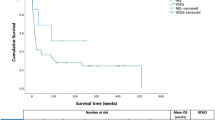

A total of 101 infants were identified though the RIS keyword search performed at two tertiary paediatric hospitals and one tertiary obstetric hospital from 2008 to January 2021. 11 patients were excluded due to no CSF diversion shunt and 22 were excluded due to the absence of hydrocephalus on imaging leaving a total of 68 patients who underwent CSF diversion for hydrocephalus. 3 patients were excluded due to the co-existence of a 3rd ventriculostomy. 7 further patients were excluded due to no blood sensitive sequences on MRI, 1 patient was excluded due to being older than 12 months of age at the time of shunting, 2 patients were excluded due to insufficient clinical information and 4 patients were excluded due to inadequate pre-operative imaging. For the remaining 51 patients, consensus neuroimaging review by three radiologists revealed 8 WHIPS patients (16%) and 43 controls (84%). The patient flow chart is shown in Fig. 1.

A comparison of the demographic and clinico-radiological characteristics between the WHIPS group and control group is presented in Table 1. There were no significant differences in gender, gestational age at birth, age at shunting, time to shunting, pre-op head circumference, % change in head circumference, BFR pre-op, BFR post-op or BFR % change between the two groups. There was a statistically significant difference between post-op head circumference between the WHIPS and control group, the WHIPS group having a larger head circumference post op compared to the control group (42.5 cm vs. 37.7 cm p = 0.04). Although not statistically significant, the WHIPS group had a lower gestational age (33.6 weeks vs. 36.7 weeks p = 0.34), older age at shunting (73 days vs. 58 days p = 0.6), longer time to shunting (18.4 days vs. 7.5 days p = 0.2), larger pre-op head circumference (42.7 cm vs. 38.3 cm p = 0.12), larger head circumference % change (3.2% vs. 1.1% p = 0.2), smaller pre-op BFR (0.45 vs. 0.51 p = 0.22) and a smaller BFR % change (-4.61% vs. -12.29% p = 0.24). WHIPS cases all had normal coagulation profiles and were not on any anticoagulant or anti-platelet medications at the time of shunting.

The shunt types and indications between the WHIPS and control groups are compared in Table 2. There was no statistically significant difference between the two groups in terms of type of shunt used (programmable vs. non-programmable, p = 0.29). A higher proportion of non-programmable shunts was used in the WHIPS group (62.5%) vs. the control group (34.1%). Comparison of the indications for shunting demonstrated a statistically significant difference, the WHIPS group more likely (p = 0.009) to be shunted for intraventricular haemorrhage (IVH) (62.5%) and infection (37.5%) compared to the control group (42.9% IVH and 2.4% infection).

Our study revealed a statistically significant positive correlation between WHIPS and a larger post-operative head circumference. Possibly as a result of the limited case numbers in our cohort, no other statistically significant differences in demographic or clinic-radiological characteristics were identified. It is worth noting, however, that the WHIPS group exhibited a lower mean gestational age, older mean age at shunting, longer mean time to shunting, larger mean head circumference, a larger pre-operative head circumference, larger head circumference % change, smaller pre-op BFR, and smaller BFR % change. Additionally, in our cohort, the WHIPS group exhibited a statistically significant association with post-haemorrhagic and post-infectious hydrocephalus compared to the control group. In Choi et al.‘s study, statistically significant associations were reported between WHIPS and corrected age < 3 months, preterm birth, absence of prior intracranial surgery, and fronto-occipital ratio [7]. Oushy et al. identified statistically significant associations between WHIPS and the etiology of hydrocephalus (aqueductal stenosis most common), type of CSF diversion (VP shunt most common), and shunt valve classification (flow control most common) [8]. Cizmeci et al. explored WHIPS in the context of serial ventricular reservoir taps in neonates, revealing statistically significant associations between WHIPS and reductions in ventricular index and thalamo-occipital distance 7 days after reservoir tap [9].